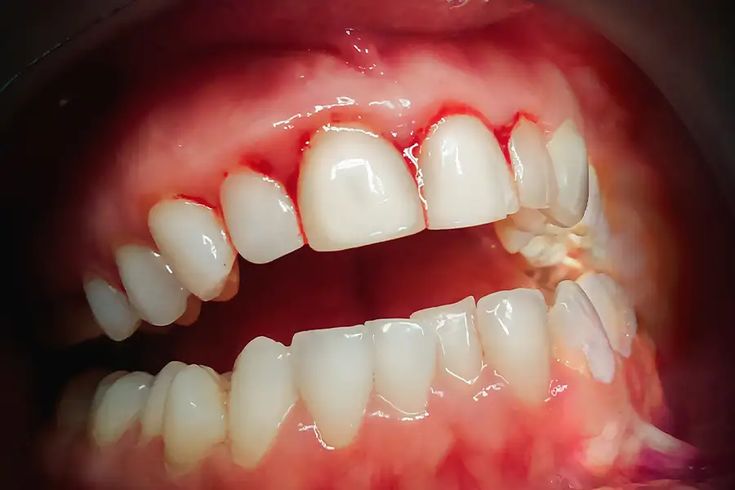

This is the early stage of gum disease. Gums may look red or swollen and may bleed during brushing or teeth cleaning. There is usually little or no pain. Gingivitis is completely reversible with proper professional care and good home cleaning.

Many people assume that bleeding gums are normal or caused by brushing too hard. In reality, bleeding is one of the earliest signs of infection. Because gum disease often causes little pain, it can quietly progress for years without being noticed.

• Gums that bleed when brushing or flossing

• Red, swollen, or tender gums